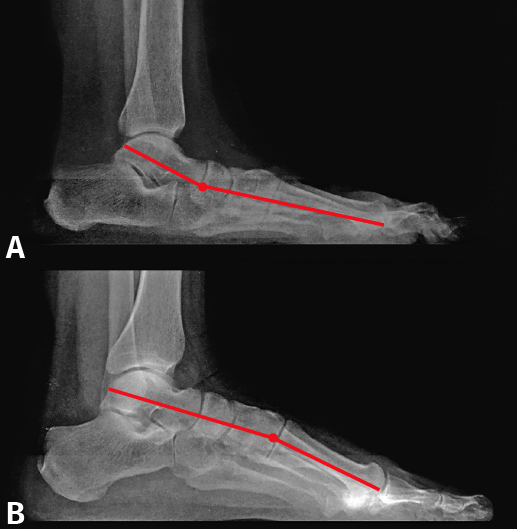

Figura 2. A: la supinación del pie plano obliga al desplazamiento del primer metatarsiano a dorsal; B: en el pie cavo, por el aumento de la bóveda plantar, el primer radio se desplaza a plantar.

Siguiendo las ideas de Paparella(5), el pie plano presenta en todos los casos una anatomía patológica uniforme: existe un doble movimiento helicoidal o rotatorio en sentido inverso, el retropié está pronado y el antepié supinado, por lo que el primer radio se encuentra en flexión dorsal (Figura 2A). A ello contribuye la pérdida de potencia del peroneo largo, el cual debido al valgo de talón tiene disminuido su brazo de palanca y, por ello, menor fuerza para la flexión plantar del primer metatarsiano. El talus está desplazado hacia abajo, delante y dentro.

M. Núñez-Samper ha estudiado un grupo de pies cavos de diversas etiologías y no encuentra tampoco diferencias morfológicas del CM y de la oblicuidad de la 1.ª ATMT, con relación a un pie normal. Al aumentar la bóveda plantar, el primer metatarsiano se sitúa en flexión plantar, es decir, verticalizado (Figura 2B).